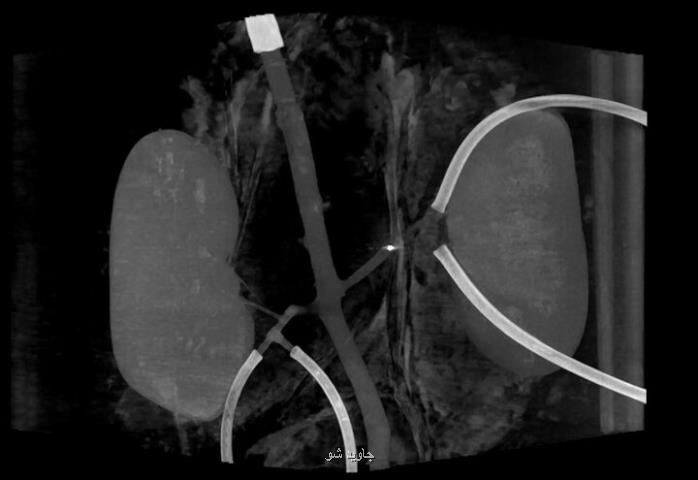

به گزارش جاوید شو به نقل از نیواطلس، هرچند برخی لخته های خونی در بدن انسان را میتوان با قراردادن ابزارهای انعطاف پذیر در رگ یا شاهرگ مورد نظر از بین برد اما دسترسی به برخی دیگر کاری مشکل است بزودی میتوان با استفاده از میلی ربات هایی که از راه دور کنترل می شوند و در رگ های بیمار حرکت می کنند لخته های خونی را درمان کرد. هم اکنون محققان دانشگاه تونته(Twente) و مرکز پزشکی دانشگاه رادبود در هلند نمونه آزمایشی این دستگاههای کوچک را ابداع نموده اند. هر ربات بدنه ای شبیه چوب پنبه کش ( یا دربازکن) دارد که با چاپگر سه بعدی ایجاد می شود و به اندازه یک دانه برنج است. در هر ربات یک آهنربای یک در یک میلیمتری قرار دارد. ایده اصلی اینست که با استفاده از کانولا یک یا چند میلی ربات در رگی که لخته خونی در آن وجود دارد، قرار گیرد. در مرحله بعد ربات از راه دور به حرکت در آید تا به لخته برسد و با سوراخ کردن، لخته را از بین ببرد. یک آهنربای درحال چرخش خارجی برای حرکت دادن ربات ها به کار گرفته می شود. همزمان با چرخیدن آهنربا، بدنه مغناطیسی شده میلی ربات در طول محور خود می چرخد و در نتیجه می تواند در خون موجود در رگ (حتی در خلاف جهت جریان خون) به سمت لخته حرکت می کند. هنگامیکه لخته از هم پاشیده می شود، جهت چرخش آهنربای خارجی معکوس می شود. این امر سبب می شود جهت حرکت میلی ربات هم معکوس شود و در نتیجه به صورت عقبگرد در رگ و به سمت منطقه ورود کانولا حرکت نماید. بدین سان میتوان آنرا از رگ خارج کرد. در آزمایش ها یک آهنربای چرخان روی بازوی رباتیک به کار گرفته شد تا چند میلی ربات را به سمت بالا و پایین در رگ های خونی متصل به شاهرگ و کلیه های یک خوک حرکت دهد. هرچند حداکثر جریان خون 120 میلی گرم به ازای هر دقیقه بود اما محققان معتقدند در صورتی که جریان خون بیشتر باشد، ربات ها با استفاده از آهنرباهای خارجی قدرتمندتر کارآمد خواهند بود. البته کاربردهای احتمالی این ابزار فقط به از بین بردن لخته در جریان خون منتهی نمی گردد. ربات ها می توانند داروها را به مناطق خاصی از بدن ببرند بدین سان عوارض جانبی دارو بر دیگر بخش های بدن اندک خواهد بود.